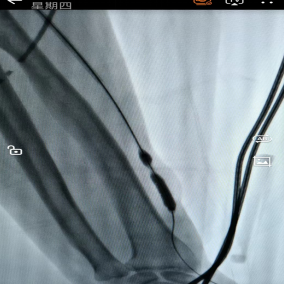

5月28日,贵州航天医院第63次晨读会由我院肾脏风湿科副主任医师李玫作学术交流,她以“类风湿关节炎的诊疗进展”为题,系统讲解了类风湿关节炎的发病机制、临床表现、实验室辅助检查、治疗方案及预后管理,重点围绕疾病诊断标准与治疗策略展开论述。在治疗领域,分别从传统药物治疗路径、生物靶向治疗新进展及外科干预时机三个维度进行阐释,并结合临床实践对治疗方案的选择原则作出说明。 肾脏风湿科专家简介 冯远军 中共党员,肾脏风湿、肝胆外科党支部书记,肾脏风湿科主任,主任医师 临床擅长:对慢性肾脏病、急性肾损伤、急慢性肾小球肾炎、肾病综合症、风湿性疾病、间质性肾炎、肾小管损伤等疾病的诊治及血液透析技术、动静脉内瘘成形术及疑难病例的诊治具有丰富的临床经验。 曾在上海市第一人民医院及贵阳市第一人民医院进修学习,贵州省医学会肾脏病学分会第五届委员会委员,遵义市医学会肾脏病学分会第一届委员会副主任委员,遵义市医学会风湿病学分会第一届委员会副主任委员,荣获“贵州航天劳动模范、遵义市汇川区先进工作者”,遵义市医疗事故鉴定专家库成员,主持省市级科研项目4项,完成4项,近5年发表论文10余篇,北大核心期刊1篇。 王卫华 肾脏风湿科主任医师 临床擅长:从事临床工作28年,擅长尿毒症患者血管通路的建设及维护(如标准和高位动静脉内瘘术、取栓+内瘘重建术、内瘘狭窄球囊扩张术、长期中心静脉置管术及肾穿刺活检术)等手术,对原发性和继发性肾病综合征、急、慢性肾小球肾炎、慢性肾脏病、泌尿系感染、结缔组织病、急性中毒、痛风、贫血、血小板减少症等疾病诊治及血液透析技术应用等具有丰富的临床经验。 1995年毕业于遵义医学院临床医学系,曾前往重庆医科大学进修学习肾脏疾病及血液净化;遵义市医学会肾脏病学分会常务委员,遵义市血液净化质量控制中心委员;先后发表肾病专业省部级医学刊物医学论文8篇,主持市级科研项目2项。 李丽华 中共党员,肾脏风湿科副主任医师 临床擅长:从事临床工作17年,对慢性肾脏病、急性肾损伤、急慢性肾小球肾炎、肾病综合征、风湿性疾病、间质性肾炎、肾小管损伤、急慢性肾衰竭的血液透析、CRRT治疗以及血管通路的建设维护等具有丰富的临床诊疗经验。 2006年毕业于遵义医学院临床专业,曾在遵义医学院附属医院完成住院医生规范化培养,并前往第三军医大学新桥医院、珠海市人民医院进修学习;中华医学会遵义市肾脏病学分会委员,遵义中医药学会肾病专业委员会委员,遵义市血液净化质量控制中心委员,遵义市医学会血液学分会委员会委员;发表省部级医学刊物医学论文4篇,主持参与省级科研课题1项,主持参与市级科研课题1项,院级新技术6项,获得本专业授权实用新型专利3项。 李 玫 中共党员,肾脏风湿科副主任医师 临床擅长:从事临床工作15年,对慢性肾脏病、急性肾损伤、急慢性肾小球肾炎、肾病综合征、风湿性疾病、间质性肾炎、肾小管损伤等疾病的诊治具有丰富的临床经验,擅长血液透析技术、动静脉内瘘成形术等。 2008年毕业于遵义医学院临床医学系,曾前往遵义医学院附属医院进修学习肾脏病与血液净化相关技术;遵义市医学会肾脏病学分会委员,发表肾病专业省部级医学刊物医学论文4篇。 肾脏风湿科简介 基本情况 贵州航天医院肾脏风湿科2017年建立,住院患者承载能力达到50人左右,透析治疗服务惠及250余人的患者群体,在学科建设、高端医疗设备引进及专业技术队伍已达到区域内领先水平。科室共有医护人员46名,副高级以上专家7名,亚专业设置齐全,涵盖肾脏疾病、风湿免疫疾病药物治疗、透析治疗及透析通路维护等多个专业领域,为患者提供全面、精准、高效的诊疗服务。配备了尖端的医疗设备与智能化的辅助系统,包括透析机、CRRT机等设备。 专科特色 (一)肾脏病治疗领域:专精于血液透析、血液透析滤过、血液灌流、血浆置换、CRRT等尖端技术,致力于为患者量身打造个性化的肾脏替代治疗方案。 (二)在风湿病治疗方面:凭借生物制剂、免疫抑制剂等前沿药物,结合患者的具体情况,精心策划个体化的治疗策略,有效减轻患者症状,显著提升生活质量。 超声引导下球囊扩张术:内瘘狭窄是内瘘最常见的并发症之一,我们采用先进的超声引导下球囊扩张术,通过微创方式恢复内瘘通畅,有效避免了传统手术带来的创伤和痛苦。 内瘘血栓溶栓治疗、取栓术:血栓形成是内瘘功能丧失的主要原因之一,根据患者具体情况,采用溶栓治疗、取栓术等多种手段,确保患者及时恢复透析治疗。 内瘘动脉瘤形成治疗:动脉瘤是由于内瘘局部血流动力学改变引起的血管扩张性疾病,采取佩戴弹力绷带、手术修复等措施,防止动脉瘤进一步发展和破裂。 内瘘感染治疗:内瘘感染是内瘘并发症中最为严重的类型之一,一般采用敏感抗生素进行抗感染治疗,严重者采取手术清创等措施。 内瘘窃血综合征治疗:是由于内瘘建立后,远端肢体血流减少引起的一系列症状,通过调整透析方案、改善内瘘血流分布及必要时重建内瘘等措施,有效缓解患者的症状并提高其生活质量。 诊疗范围 擅长治疗急慢性肾炎、肾病综合征、肾衰竭等肾脏疾病;擅长治疗类风湿关节炎、系统性红斑狼疮、干燥综合征等风湿免疫性疾病,并为患者提供健康教育与康复指导,帮助患者更好地管理疾病,提高生活质量。 end